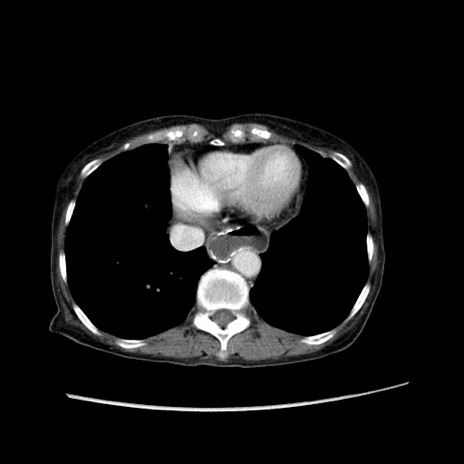

症例25(横断像)

【症例】80歳代女性

【主訴】胸のつかえ感

【現病歴】約9時間前に食後から胸のつかえた感じあり、嘔吐あり、来院。

【既往歴】胃癌(全摘)、胆摘、虫垂炎

【身体所見】心窩部に圧痛あり、反跳痛なし。

【データ】WBC 5700、CRP 0.05